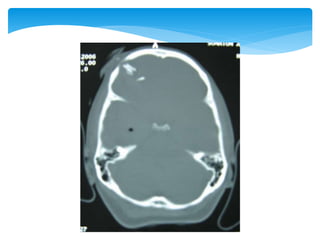

 Between thedura mater and arachnoid membrane  Tearing of bridging veins  Severe brain damage more likely than with epidural haematomas  Approximately 60%, but can be lowered with rapid surgical intervention and aggressive medical management Subdural Haematomas

Approach To CT ScanCT scan

Approach To CTScanCT scan Bone window Look for fractures- •Cranial vault •Skull base •Facial bones Tissue window •EDH •SDH •ICH •Contusions •Pneumocephalus •Hydrocephalus •Cerebral edema Subdural window •Any hemorrhage •Soft tissue and bone •Fontanel •Suture lines •Foreign bodies